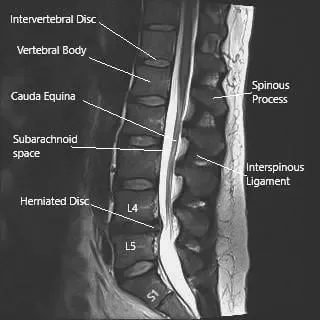

Imagen por resonancia magnética de la columna lumbosacra en sección sagital que muestra una hernia de disco intervertebral a nivel L4-L5.

El gran tamaño y la trayectoria larga del nervio ciático lo hacen especialmente vulnerable a la compresión o a lesiones. La causa más común de irritación es una hernia de disco en los niveles L4–L5 o L5–S1 , que puede comprimir una o más raíces nerviosas contribuyentes. Otras causas incluyen estenosis espinal, enfermedad degenerativa del disco, síndrome piriforme y traumatismos directos.

La resonancia magnética es la herramienta de imagen más eficaz para evaluar la patología del nervio ciático. Puede detectar hernias discales, estrechamiento del canal espinal y compresión de la raíz nerviosa a nivel lumbossacro. También pueden utilizarse tomografías computarizadas y electromiografías (EMG) para identificar causas relacionadas con los hueos o evaluar la función nerviosa.

Una resonancia magnética de la columna lumbosacra suele revelar la fuente de la compresión: lo más común es una hernia de disco a nivel L4–L5 que presiona una de las raíces nerviosas contribuyentes.